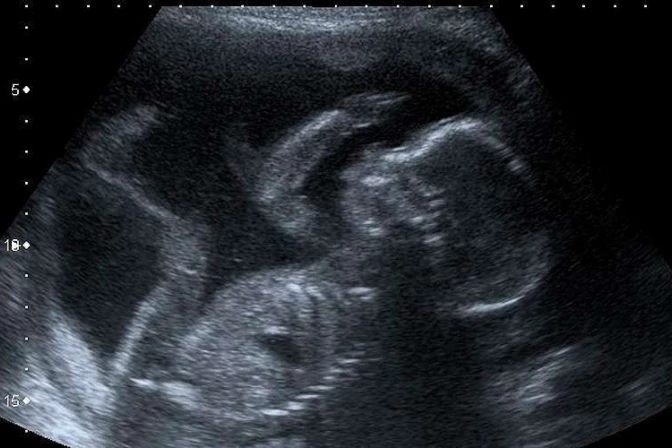

En su columna, el Obispo explicó a los costarricenses que "en cuanto al inicio de la vida humana, se considera la concepción como el comienzo de la misma, el principio de un nuevo ser. Mediante la concepción, aquel que no era ya es. La vida individual de una nueva criatura humana surge de los dos elementos que la constituyen".

"El óvulo y el espermatozoide contribuyen a la preparación de esta nueva vida, sin que se dé ningún momento intermedio; por esto, hablar de 'óvulo fecundado' puede dar la impresión de que la concepción se trata sólo de un cambio en el estado del óvulo, de no fecundado a fecundado, cuando en realidad con el cigoto inicia la existencia de un nuevo ser humano irrepetible".

En ese sentido, señaló que "hoy sabemos que el cigoto y el embrión se desarrollan no sólo en dirección del individuo humano, sino que se desarrollan desde su inicio como individuo humano".

Por consiguiente, afirmó, "el embrión humano no es una cosa, sino que es alguien que, poco a poco, podrá decir 'yo' uniendo su propia existencia con sus inicios en el seno materno. La identidad de cada ser humano, desde el aspecto genético hasta el psicológico, es una realidad que en cada uno de nosotros sabemos iniciada en la concepción".

"Así, en nuestro hablar ordinario consideramos el inicio de nuestra existencia en la concepción de cada uno, pues, antes de ésta, no existíamos. Cuando fuimos concebidos no estábamos presentes, pero una vez concebidos nos hicimos presentes. Nadie niega su propia identidad con la del embrión que un día fue en el seno materno", indicó.

Mons. Garita dijo que "todo el proceso del desarrollo del embrión debe entenderse no sólo como un puro proceso biológico, sino como un proceso biológico-humano. Desde la concepción, la existencia humana es un proceso continuo que se subdivide en varias fases que forma una única y misma persona, idéntica a sí misma".